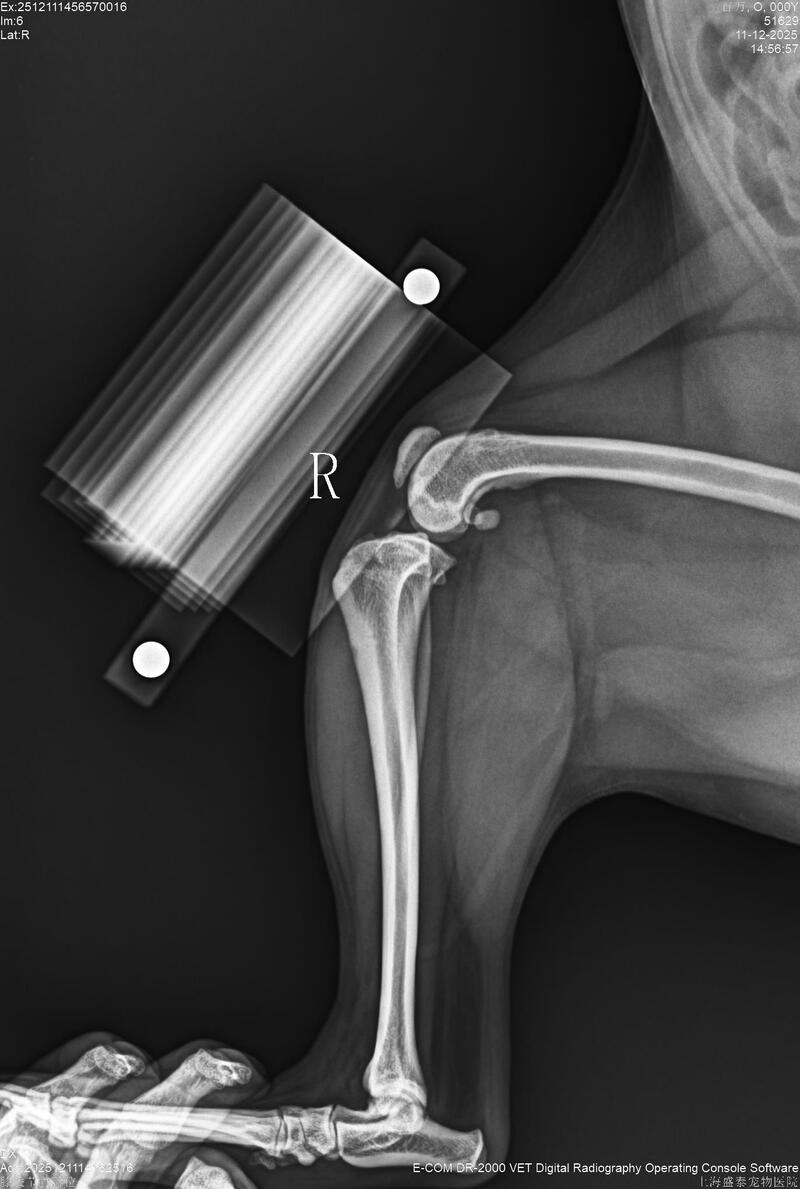

一周前突然出现左后肢跛行,左前十字韧带断裂左髌骨4级脱位右3级脱位,决定进行双侧滑车沟置换与TPLO手术治疗。

术中采用BlueSAO佰陆生物型滑车沟置换系统(PGR)#4植入物进行置换,并使用BlueSAO佰陆TPLO- 7 mmL纯钛锁定骨板进行内固定。手术损伤小,恢复才会快,术后3天可以负重走路,望早日康复